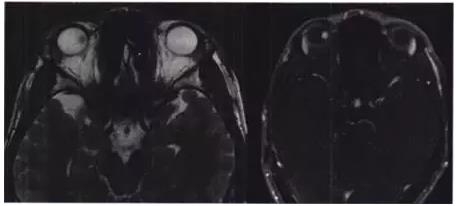

UBM示双眼前段未见明显异常。MRI示右眼内上壁异常信号,呈等T1、等T2信号影,增强未见明显强化(图4)。

图4 右眼视力下降患者右眼眶MRl险查结果